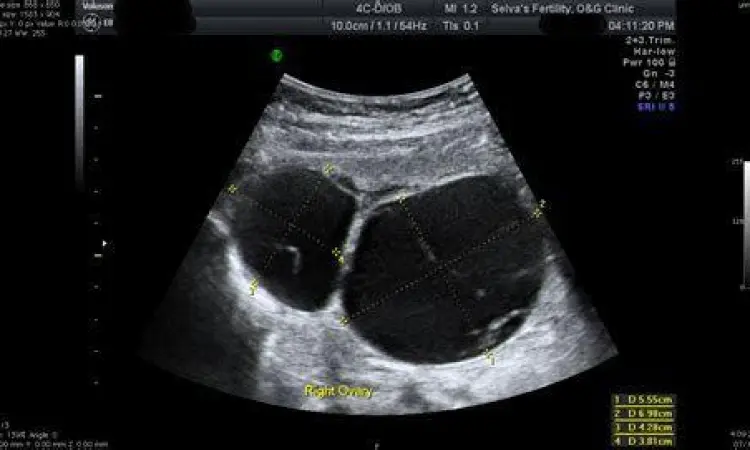

Kista ovarium adalah jenis yang paling sering dibicarakan dan bisa menyerang wanita pada usia subur maupun setelah menopause. Ciri ciri kista ovarium sering kali tidak terlihat dari luar, namun penderita mungkin merasakan tekanan di perut bagian bawah. Jika kista tersebut berukuran besar atau mengalami puntiran (torsi), gejala yang muncul bisa berupa nyeri panggul yang tajam sebelum atau selama siklus menstruasi, perut kembung yang tidak kunjung reda, serta frekuensi buang air kecil yang meningkat akibat tekanan kista pada kandung kemih.

Setelah mengenali indikasi awal, langkah medis selanjutnya adalah melakukan penegakan diagnosis. Dokter biasanya akan memulai dengan palpasi fisik untuk merasakan tekstur benjolan. Untuk kista internal, pemeriksaan ultrasonografi (USG) adalah metode yang paling umum digunakan karena dapat membedakan dengan jelas antara massa cair (kista) dan massa padat. Dalam beberapa kasus, dokter mungkin melakukan aspirasi jarum halus (Fine Needle Aspiration) untuk mengambil sampel cairan guna diuji di laboratorium.